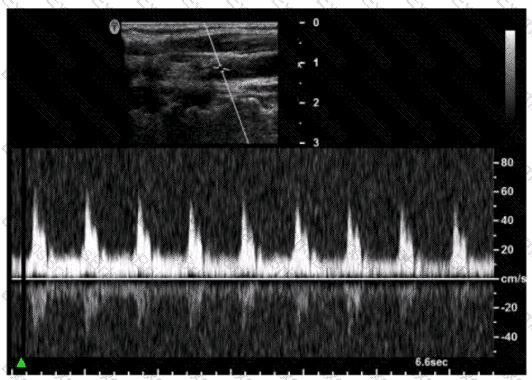

Questions 3

How can the spectral Doppler mirroring seen in this image be eliminated?

Options:

A.

Decrease wall filter.

B.

Decrease Doppler gain.

C.

Increase dynamic range.

D.

Increase pulse repetition frequency (PRF).